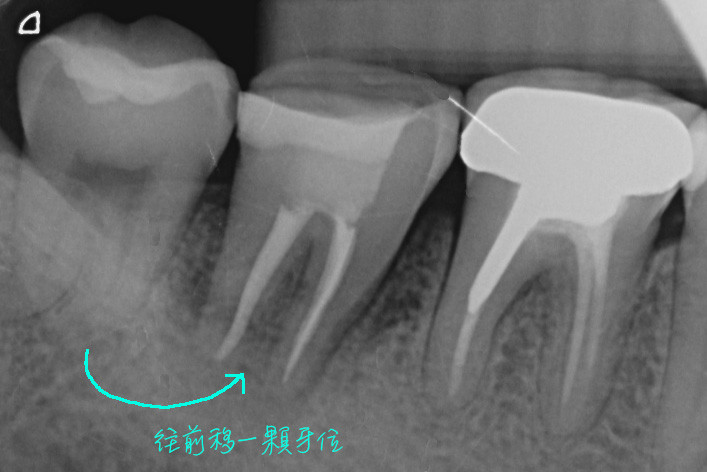

本案例的臼齒因為斷裂而必須拔除,我們把後方的智齒往前搬家,直接取代壞掉的牙齒,等到傷口癒合好後又可以正常咀嚼食物了。